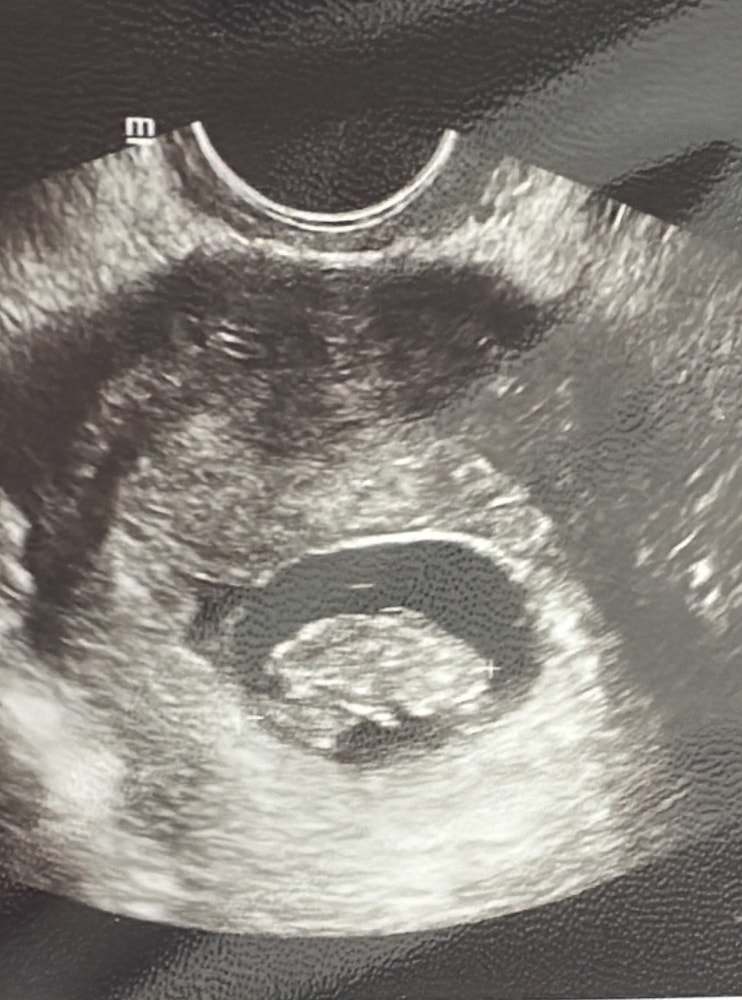

Не понравился мой двух часовой ктг 🥺 вообще не понимаю , что происходит. Сижу в приемном отделении коммунарки …очень надеюсь 🤞 что все хорошо . В ЖК поставили острую гипоксию плода , тахикардию …страааашно

малышка выросла за 2 недели на 350гр ❤️ ее мать похудела на 200гр😅

предположительная масса плода 2400. Врач сказала , что к 37-38н будет 3300 примерно 😄 ну вот это я понимаю , так и рожала своих девочек на этом сроке 🤗 младшая дочь уже вся извелась 🤣ждет сестру , аж в пупок кричит - скоро май !!!! Слышишь ???!!!😅

Сахар стал каким-то ровным даже после еды . Ночью опускался в красную зону , убрала 2ед. Так совпало , что сахар стал ниже обычного вместе с болью в желудке (тошнота ). Вроде как все в пределах нормы , но непривычно видеть такую линию в графике . Да и самочувствие ужасное совпало с этим . Плацента степень зрелости 1. На либре 4-5;5 целый день